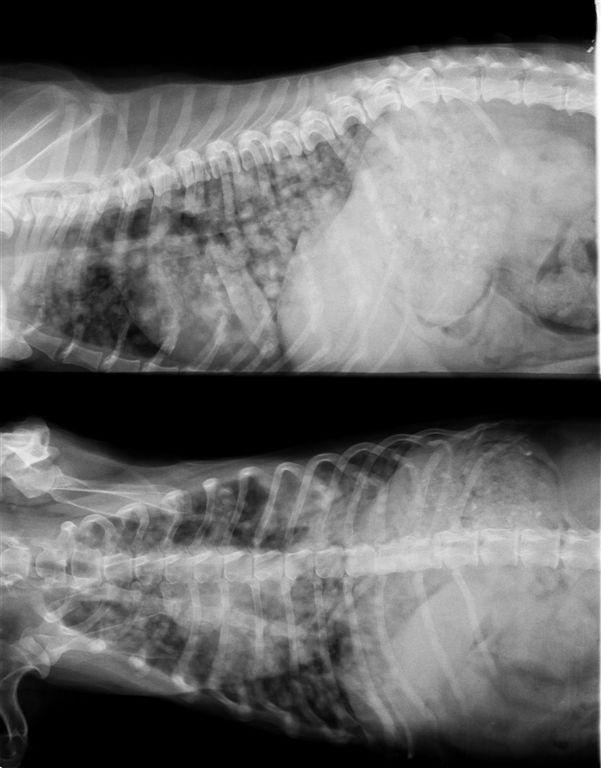

13歳 猫 メス

診断:乳腺腺癌

肺後葉に7mm大の転移像が見られる

。

手術後6ヶ月定期検査で発見された。猫の乳腺癌は1cm以下の段階でも遠隔転移を考慮に入れたほうがよい